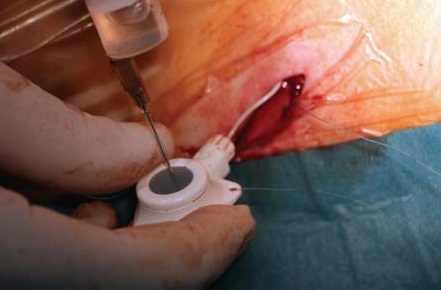

Методика имплантации. Пациенту выполнена люмбальная пункция в проекции L1-сегмента иглой Туохи парамедианным доступом. Интратекально в краниальном направлении заведен спинальный катетер на 6 см. Проведена морфиновая проба (в субарахноидальное пространство введено 100 мкг морфина). Через несколько минут пациент отметил уменьшение болевого синдрома по НОШ с 80 до 10%. На этом фоне пациент смог безболезненно повернуться на спину. Морфиновая проба рассмотрена как положительная, имплантирована порт-система «B|Braun Celsitest 304-20». Камера порта выведена подкожно по передней подмышечной линии в проекции пятого межреберья. Последовательность ключевых этапов манипуляции представлена на рисунках 1–8.

Рис. 8. Общий вид имплантированной спинальной порт- системы с установленным в нее катетером на игле Губера после ушивания дефекта кожи

Камера порта контурирует с целью ее свободного и быстрого нахождения пациентом. Пациент после простого инструктажа сам вводил себе растворы лекарственных средств.